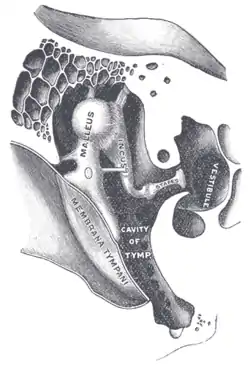

External and middle ear, opened from the front. Right side. Chain of ossicles and their ligaments, seen from the front in a vertical, transverse section of the tympanum.

Chain of ossicles and their ligaments, seen from the front in a vertical, transverse section of the tympanum. CT image of malleus